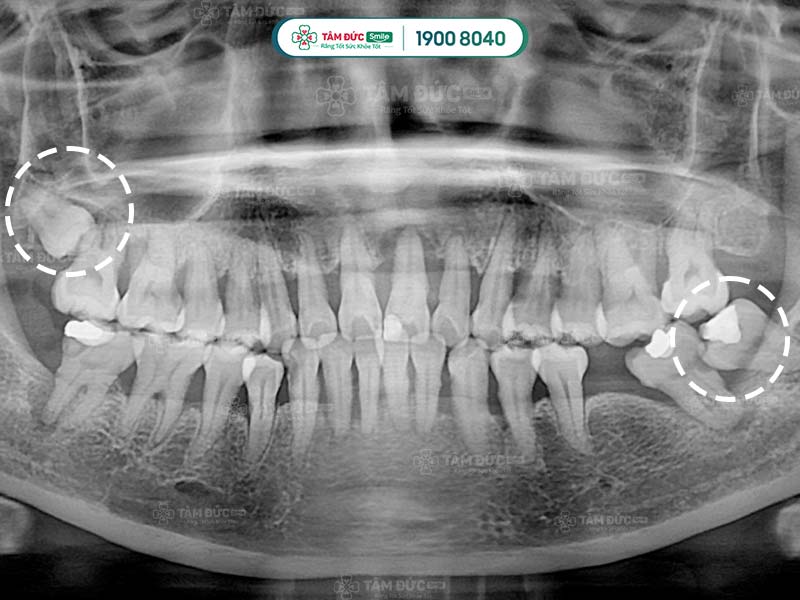

Răng khôn mọc lệch nên nhổ từ sớm

10.1. Chụp phim và tư vấn

Đây là bước quan trọng nhất trong quy trình nhổ răng khôn an toàn. Quý khách cần chụp phim X-quang để bác sĩ xác định vị trí và tư thế của răng khôn. Qua đó, bác sĩ dễ dàng đưa ra phương án nhổ răng an toàn nhất.